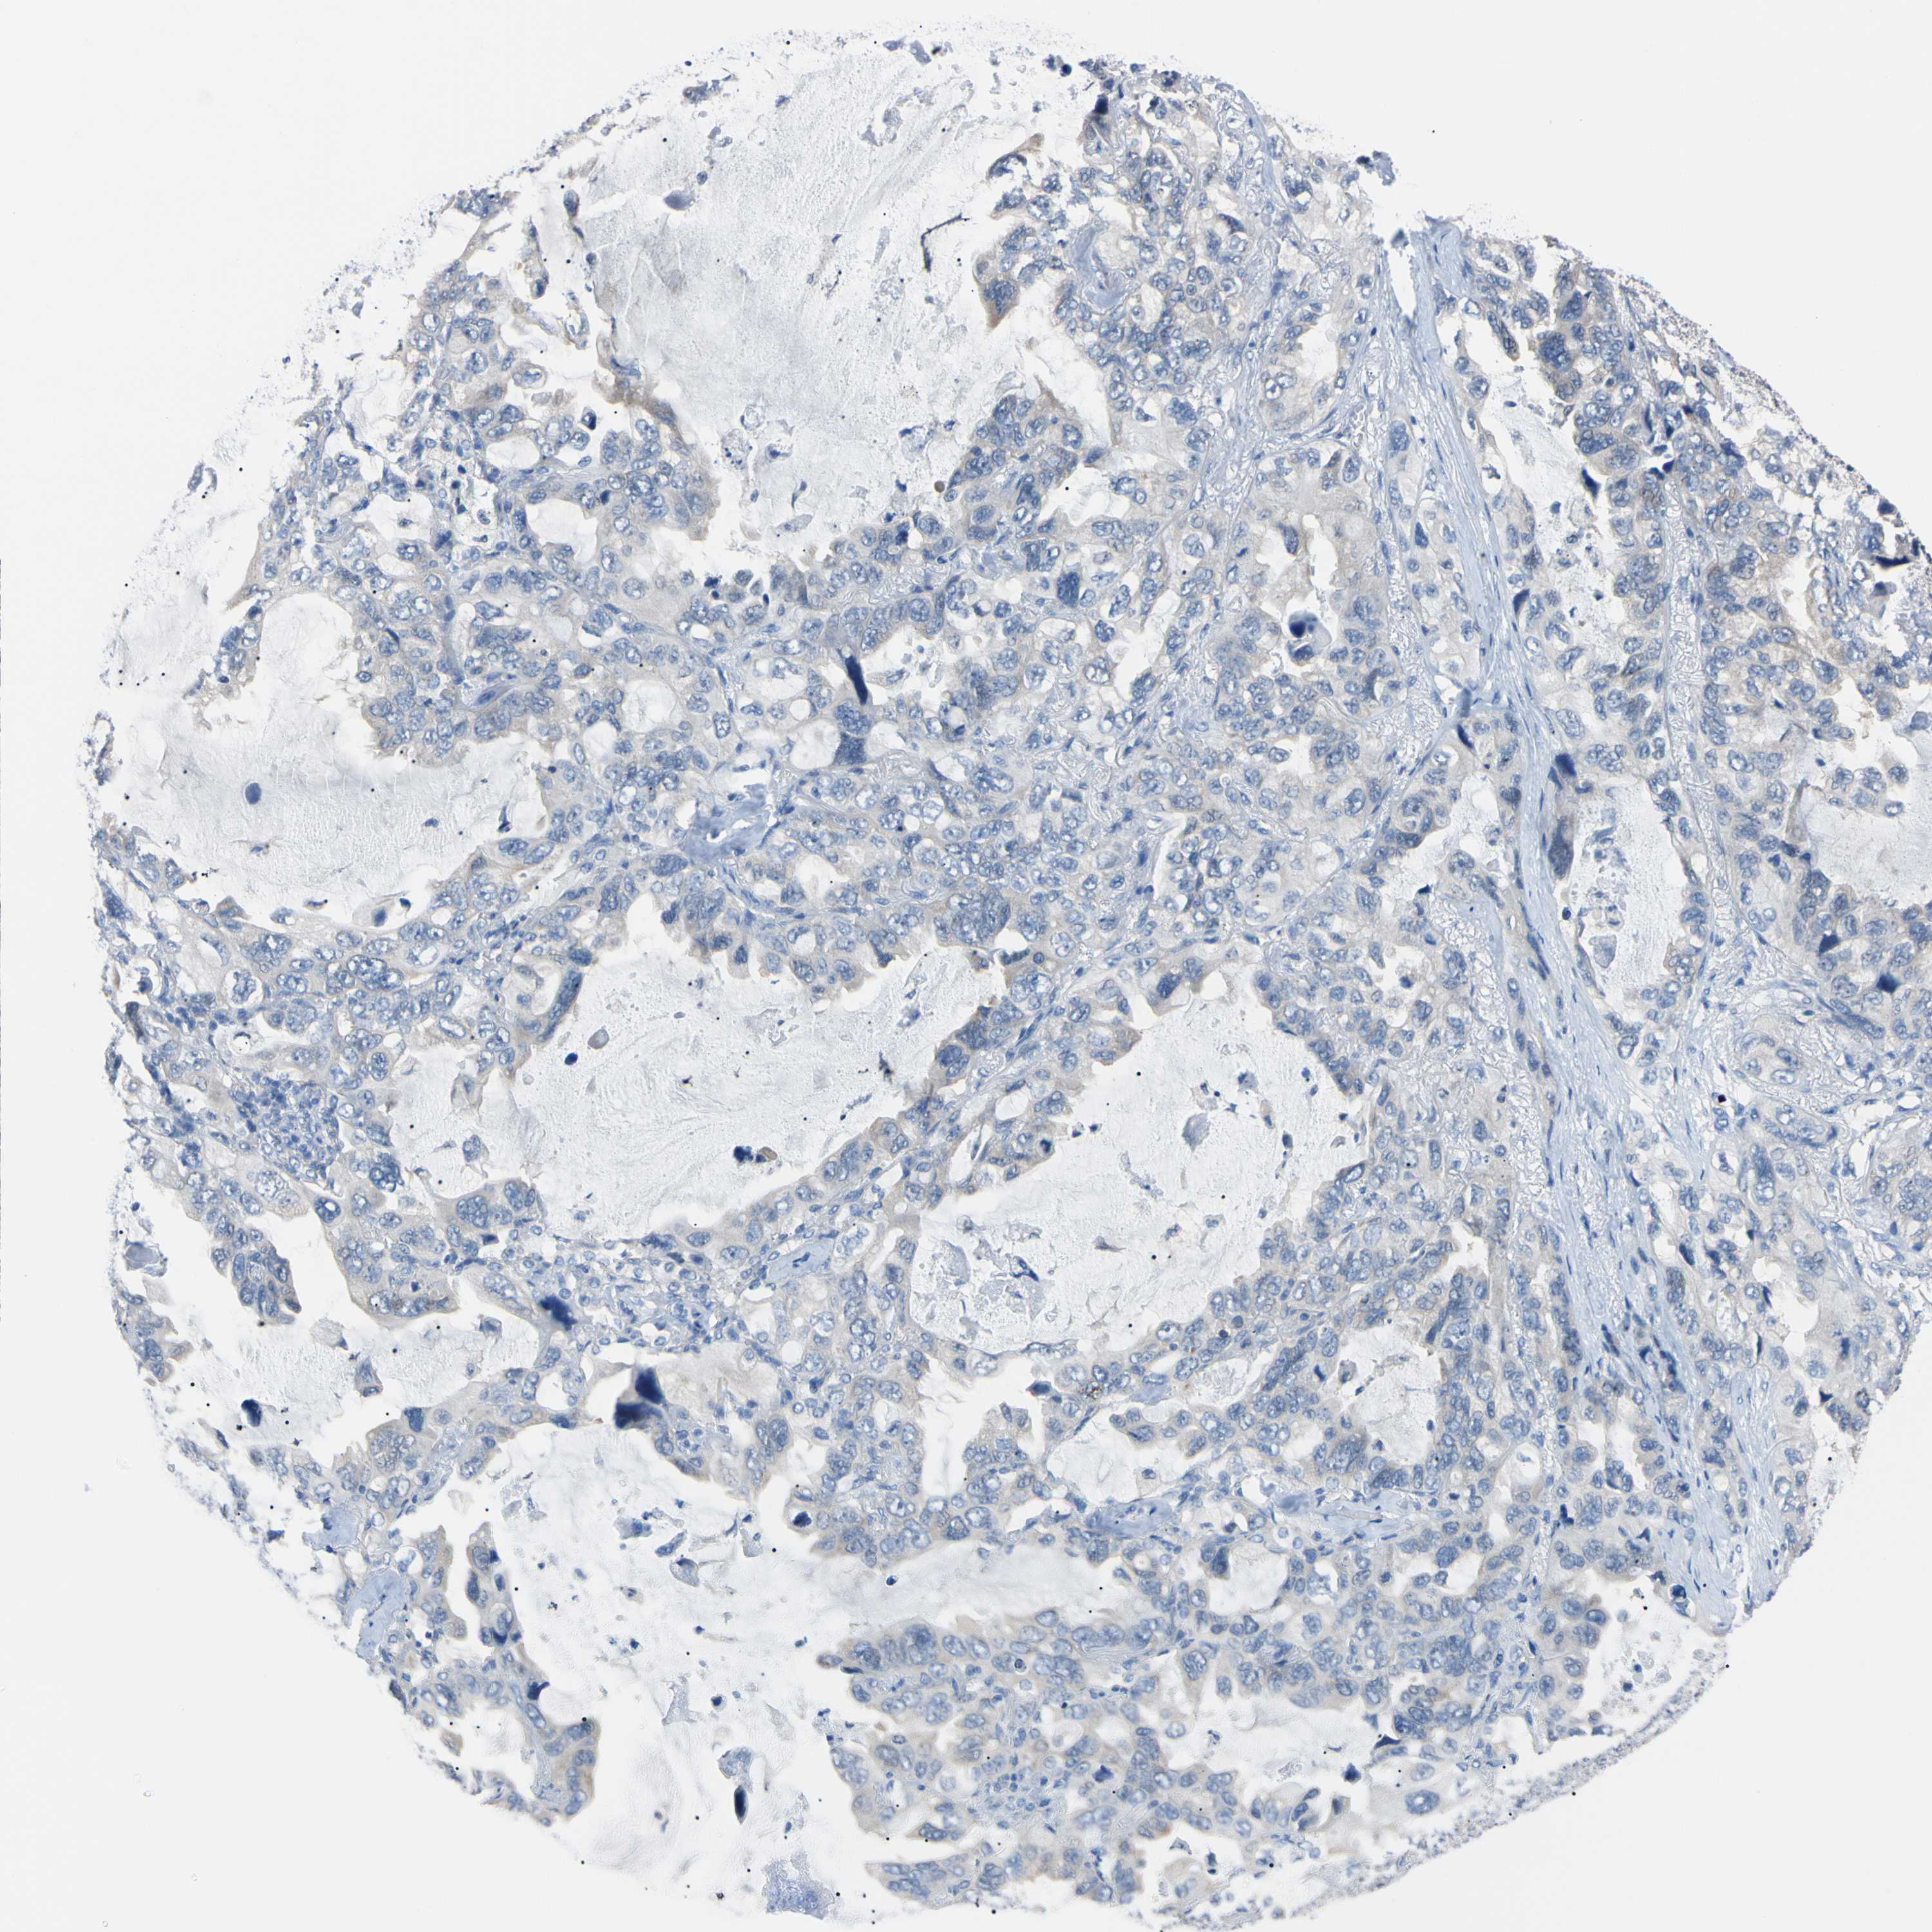

LUNG SQUAMOUS CELL CARCINOMA (TCGA) - Interactive survival scatter ploti

The Survival Scatter plot shows the clinical status (i.e. dead or alive) for all individuals in the patient cohort, based on the same data that underlies the corresponding Kaplan-Meier plots. Patients that are alive at last time for follow-up are shown in blue and patients who have died during the study are shown in red.

The x-axis shows the expression levels (FPKM) of the investigated gene in the tumor tissue at the time of diagnosis. The y-axis shows the follow-up time after diagnosis (years). Both axes are complimented with kernel density curves demonstrating the data density over the axes. The top density plot shows the expression levels (FPKM) distribution among dead (red) and alive patients (blue). The right density plot shows the data density of the survived years of dead patients with high and low expression levels respectively, stratified using the cutoff indicated by the vertical dashed line through the Survival Scatter plot. This cutoff is automatically defined based on the FPKM cutoff that minimizes the p-score. The cutoff can be changed by dragging the vertical line or by entering a cutoff value in the square labeled "Current cut-off".

Under the Survival Scatter plot the p-score landscape (black curve; left axis) is shown together with dead median separation (red curve; right axis). Dead median separation is the difference in median mRNA expression between patients who have died with high and low expression, respectively. It is calculated as follows: median FPKM expression of dead patients with high expression - median FPKM expression of dead patients with low expression. This is intended to aid the user in visually exploring custom cutoffs and the associated p-scores and dead median separation.

Individual patient data is displayed and can be filtered by clicking on one or more of the category buttons on the top of the page. Categories describing expression level and patient information include: high, low, alive, dead, female, male and tumor stages. The scale of the x-axis can be toggled between linear and log-scale by clicking on the "x log" button. Mouse-over function shows TCGA ID, patient information and mRNA expression (FPKM) for each patient.

& Survival analysisi

Kaplan-Meier plots summarize results from analysis of correlation between mRNA expression level and patient survival. Patients were divided based on level of expression into one of the two groups "low" (under cut off) or "high" (over cut off). X-axis shows time for survival (years) and y-axis shows the probability of survival, where 1.0 corresponds to 100 percent.

RARS1 is not prognostic in Lung Squamous Cell Carcinoma (TCGA)

: 44.44

P scorei

N/A

Average pTPM 42.6

Number of samples 489